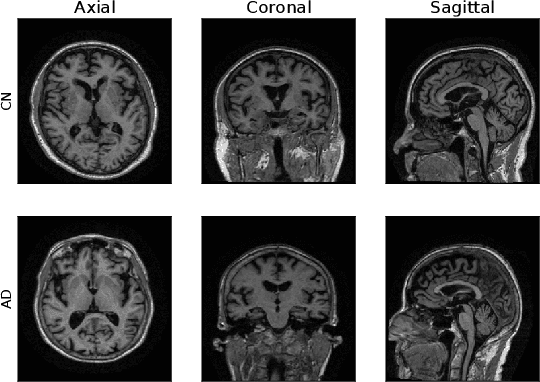

Abstract:Machine Learning (ML) has emerged as a promising approach in healthcare, outperforming traditional statistical techniques. However, to establish ML as a reliable tool in clinical practice, adherence to best practices regarding data handling, experimental design, and model evaluation is crucial. This work summarizes and strictly observes such practices to ensure reproducible and reliable ML. Specifically, we focus on Alzheimer's Disease (AD) detection, which serves as a paradigmatic example of challenging problem in healthcare. We investigate the impact of different data augmentation techniques and model complexity on the overall performance. We consider MRI data from ADNI dataset to address a classification problem employing 3D Convolutional Neural Network (CNN). The experiments are designed to compensate for data scarcity and initial random parameters by utilizing cross-validation and multiple training trials. Within this framework, we train 15 predictive models, considering three different data augmentation strategies and five distinct 3D CNN architectures, each varying in the number of convolutional layers. Specifically, the augmentation strategies are based on affine transformations, such as zoom, shift, and rotation, applied concurrently or separately. The combined effect of data augmentation and model complexity leads to a variation in prediction performance up to 10% of accuracy. When affine transformation are applied separately, the model is more accurate, independently from the adopted architecture. For all strategies, the model accuracy followed a concave behavior at increasing number of convolutional layers, peaking at an intermediate value of layers. The best model (8 CL, (B)) is the most stable across cross-validation folds and training trials, reaching excellent performance both on the testing set and on an external test set.